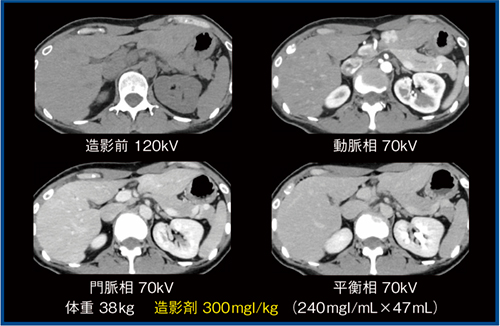

ファントム検証の結果を基に,当院では,PIQEを適用し低管電圧で造影剤投与量を40〜50%低減したプロトコールでの腹部ダイナミックCT撮影を開始した。ヨード量600mgI/kgを規準として,体重70kg以下では70kVの撮影でヨード量は50%減の300mgI/kg,体重71kg以上では十分な管電流を確保するため80kVで撮影し,ヨード量は40%減の360mgI/kgとした。

実際の画像を供覧する。症例1は,肝左葉外側区にある限局性結節性過形成疑いの多血性結節である(図4)。動脈相で濃染し,門脈相,平衡相で周囲肝実質と等吸収を呈しており,被膜構造は認めない。造影剤量を半減しても,診断には何ら影響がないことは明らかである。

なお,造影剤量が同じであれば,70kVでは120kVの2倍の造影効果が得られるため,70kV PIQEは造影効果の増強を目的とした使用も可能である。